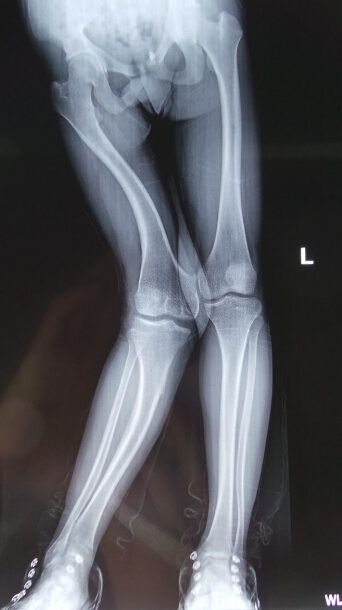

截骨導板輔助完成膝關節內外矯形截骨手術

膝關節內外矯形截骨病例,傳統的手術矯形截骨術都是通過醫生的經驗及術前在X線片上的測量得到需要截骨的多少,同時手術過程中會由于醫生的經驗不同及機械性誤差而導致術后截骨的精確度不高。現在我們通過影像數據重建患者病理模型,然后打印出患者病理骨骼模型。同時運用設計軟件,根據膝關節的解剖關系進行矯形截骨導板的設計,并打印出截骨導板。然后經過消毒后用截骨導板進行手術操作,實現精確截骨,恢復下肢力線,最終使得恢復正常力線實現矯正畸形。該項技術克服了患者骨骼畸形行常截骨矯形術依靠醫生手術經驗及機械性誤差導致的截骨不精準、手術時間長等缺點。依靠數字化技術大大提高手術精準度及質量,減少手術時間,降低了手術風險